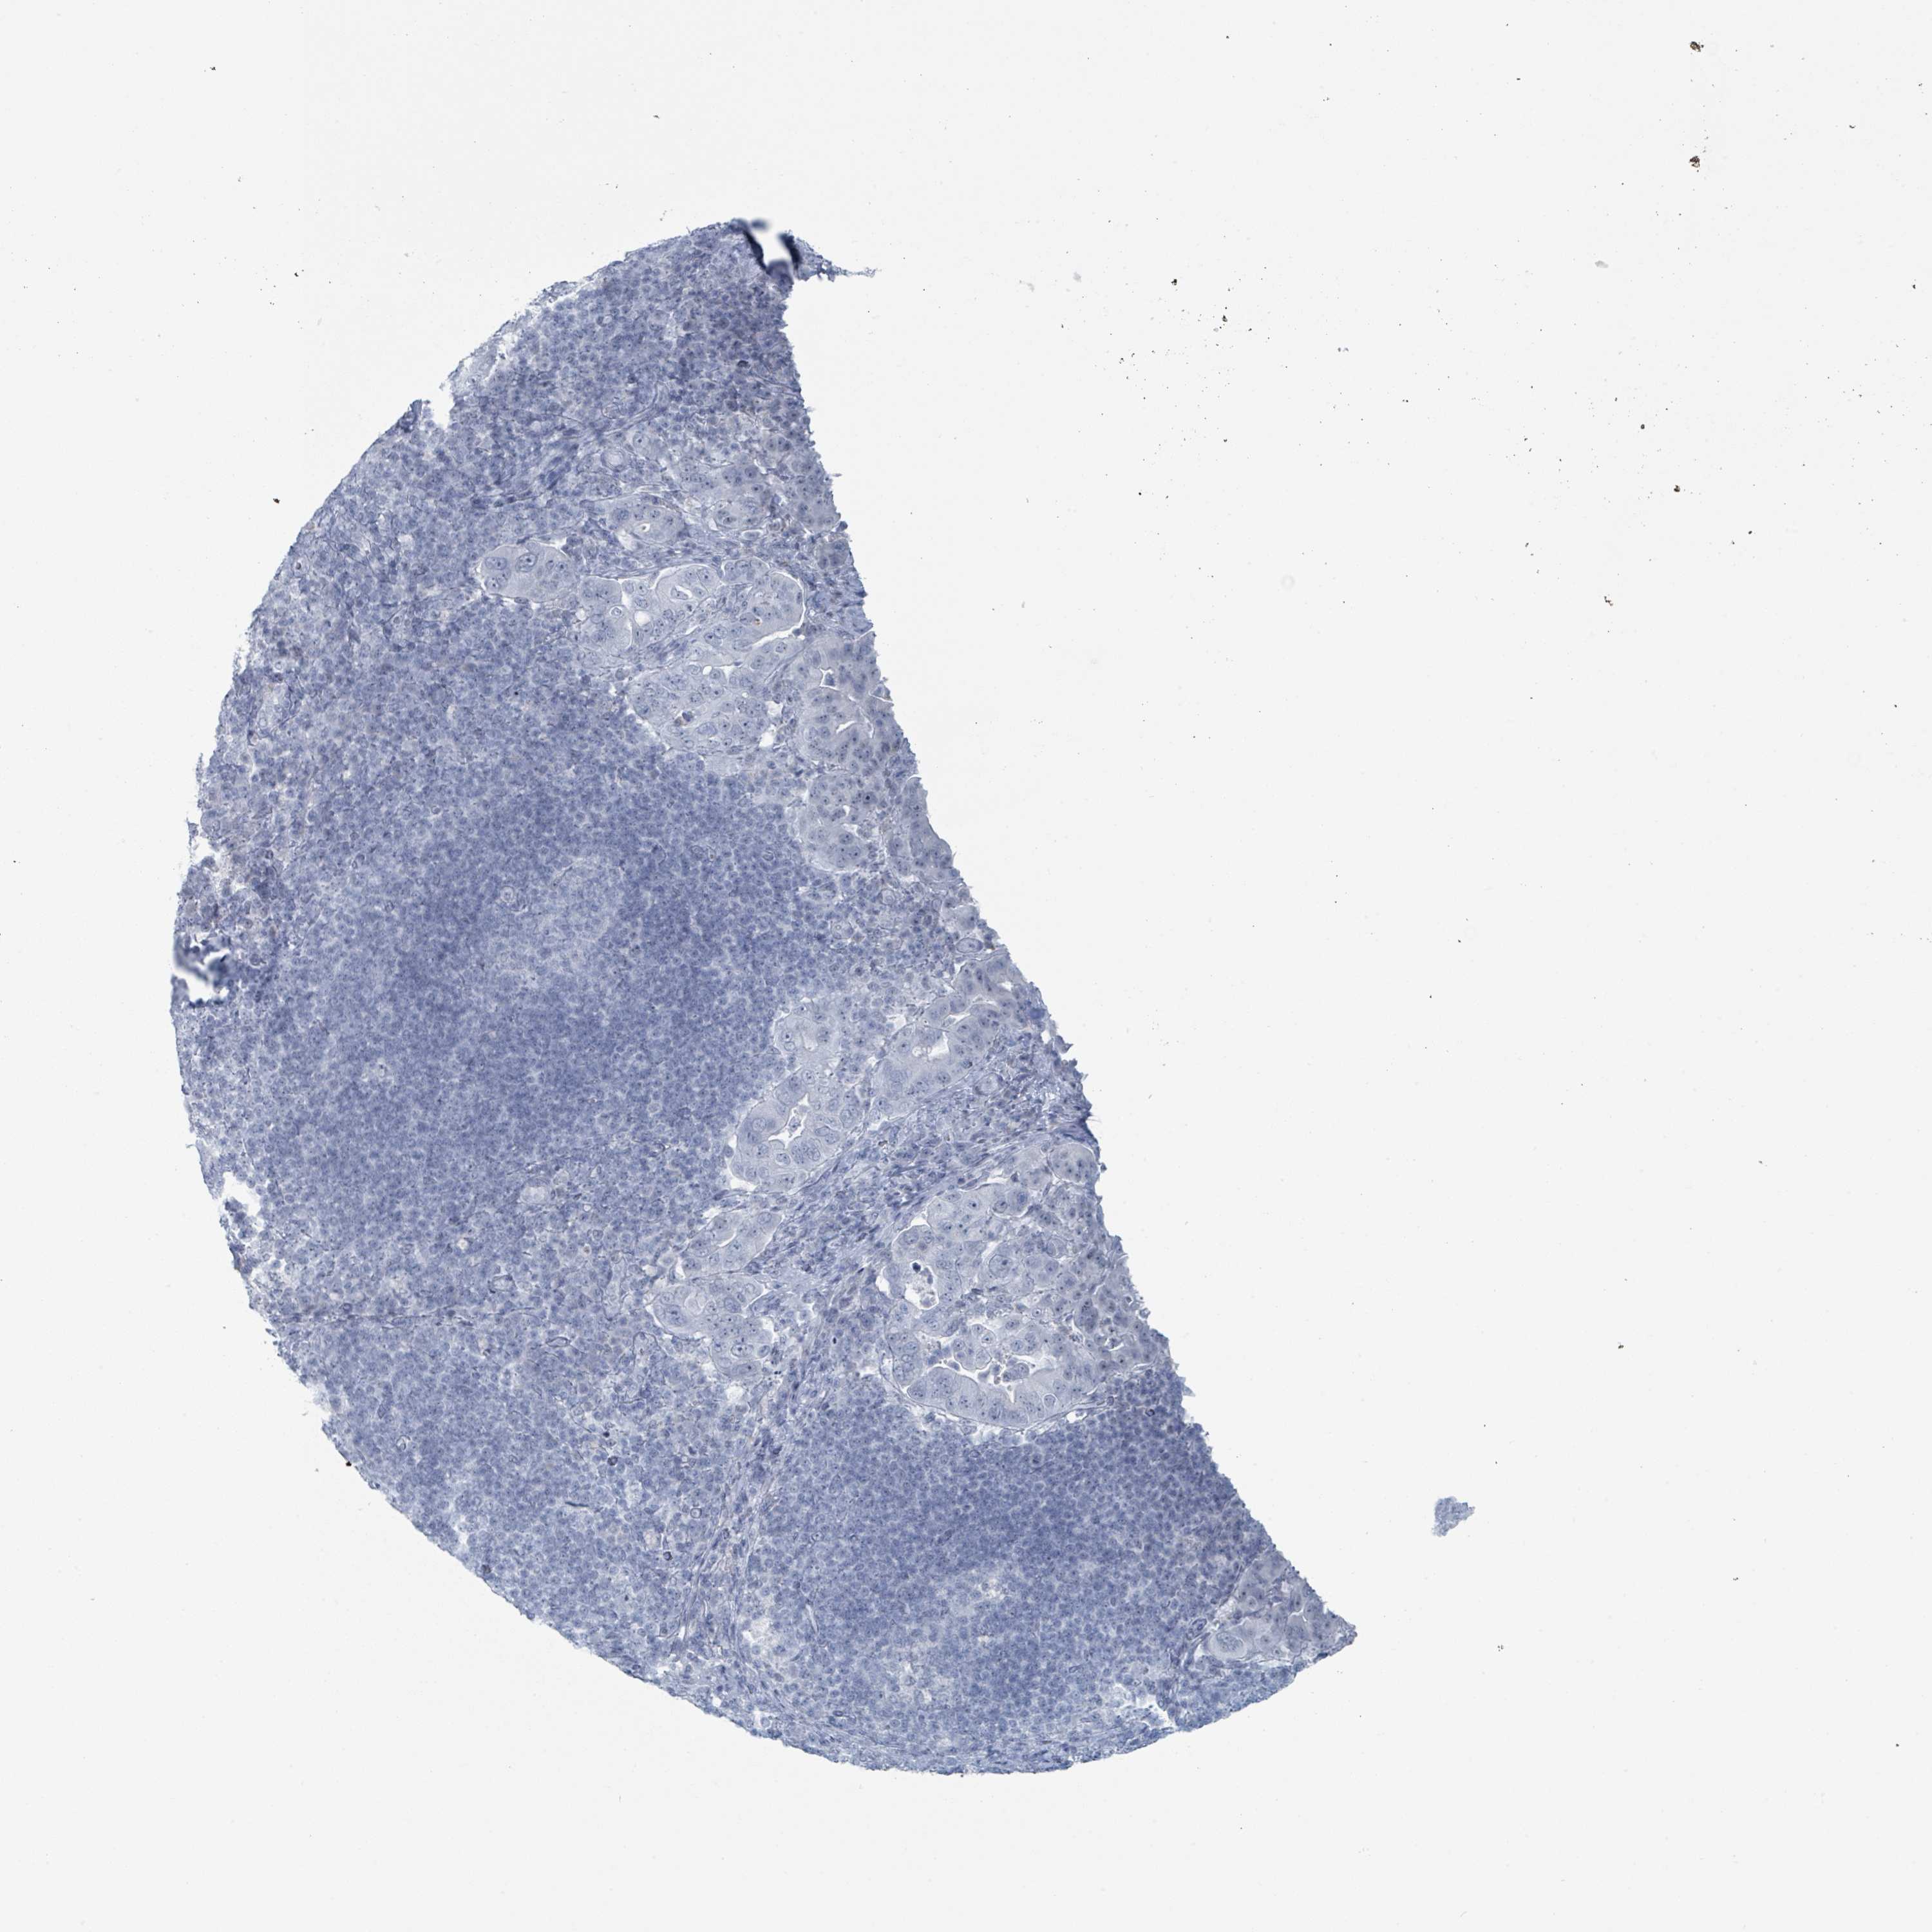

PANCREATIC CANCER - Protein expressioni

A mouse-over function shows sample information and annotation data. Click on an image to view it in a full screen mode. Samples can be filtered based on level of antibody staining by selecting one or several of the following categories: high, medium, low and not detected. The assay and annotation is described here.

Note that samples used for immunohistochemistry by the Human Protein Atlas do not correspond to samples in the TCGA dataset.

Antibody stainingi

Antibody staining in the annotated cell types in the current human tissue is reported as not detected, low, medium, or high, based on conventional immunohistochemistry profiling in selected tissues. This score is based on the combination of the staining intensity and fraction of stained cells.

Each image is clickable and will lead to virtual microscopy that enables deeper exploration of all samples and also displays staining intensity scores, fraction scores and subcellular localization as well as patient and tissue information for each sample.

Antibody HPA050920

Staining

High

Medium

Low

Not detected

Intensity

Strong

Moderate

Weak

Negative

Quantity

>75%

75%-25%

<25%

None

Location

Nuclear

Cytoplasmic/membranous

Cytoplasmic/membranous,nuclear

Adenocarcinoma, NOS